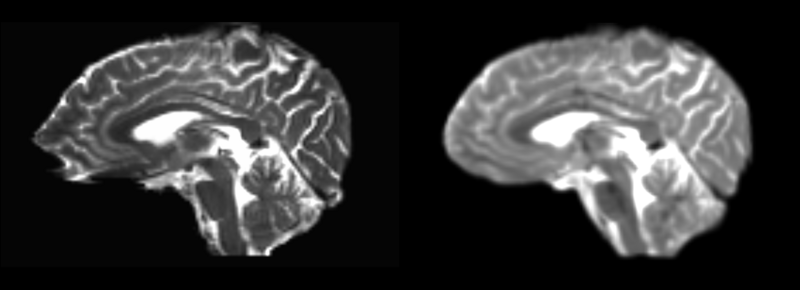

Structural image registered to corresponding DTI baseline via linear, then rigid, then bspline registration modules.

current18:44, 13 May 2009Thumbnail for version as of 18:44, 13 May 20091,160 × 420 (180 KB)Rauscha (talk | contribs)Structural image registered to corresponding DTI baseline via linear, then rigid, then bspline registration modules.